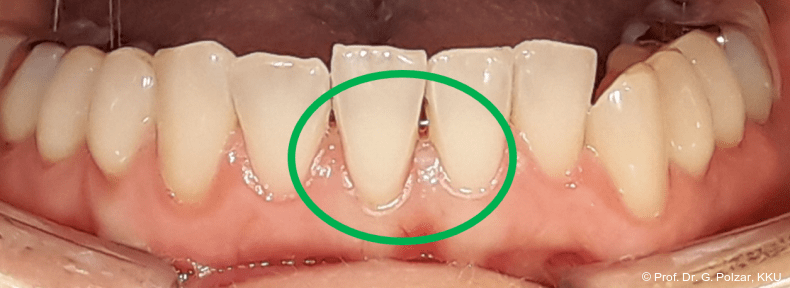

Der intraorale Befund zeigte eine scheinbar neutrale Verzahnung. Trotz Lingualretainer in der UK-Front war ein Engstand in der Unterkieferfront mit leichter Protrusion erkennbar. Appro­ximal des Zahnes 41 waren deutliche schwarze Dreiecke zu erkennen, zudem wies der Zahn eine leichte gingivale Rezession auf (Abb. 3a–f).

Diese deutlich anteriore Gelenkposition im Neutralbiss ließ den Verdacht auf einen Sunday Bite zu. Das heißt, die Patientin schob den Unterkiefer aktiv nach vorne, um damit schönere Schneidezahnkontakte bzw. eine vermeintlich neutrale Okklusion zu erreichen. Nach mühsamen Lockerungsübungen gelang es der Patientin, auch in die zen­trale Kiefergelenkposition zu wechseln. So zeigte sich das ganze Ausmaß der Malokklusion. In neutraler KG-Position hatte die Patientin eine sagittale Frontzahnstufe von ca. 7 mm mit 1 PB Klasse II-Okklusion im Seitenzahn­bereich (Abb.5a+b, 7a–c).